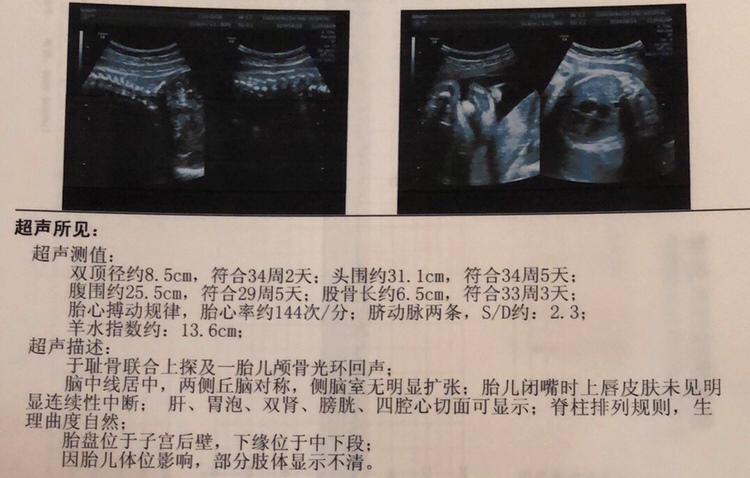

为啥我36双顶才89。。。。